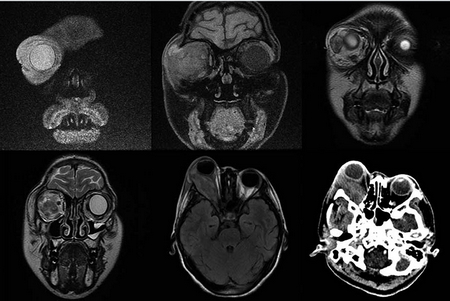

La ultrasonografía ocular reportó una lesión heterogénea que ejercía compresión y desplazamiento en sentido anterior del globo ocular derecho, y datos de inflamación de tejidos blandos (Figura 1). La tomografía computada describió la lesión como heterogénea e identificó datos de sinusitis y proptosis (Figura 2). Por resonancia magnética se reportó la misma lesión con aspecto heterogéneo de 5.5 ' 2.5 cm en sus diámetros mayores, que involucró tejidos musculares y con efecto de masa sobre estructuras orbitarias. No se observó extensión intracraneal, a cavidades paranasales ni al seno cavernoso (Figura 3). Ante una proptosis de rápida evolución y sospecha de probable rabdomiosarcoma se realizó biopsia transconjuntival de lesión intraconal y tejido peri-orbitario. Las preparaciones histológicas de la lesión intraconal y de la grasa orbitaria mostraron tejidos blandos con un proceso inflamatorio, necrótico con vasculitis de vasos de pequeño calibre con afección ocasional a vasos arteriales y venosos de mayor calibre. La vasculitis fue a expensas de linfocitos e histiocitos con trombosis aislada y algunos granulomas mal constituidos. El proceso inflamatorio estaba constituido por linfocitos, histiocitos, células plasmáticas y en una zona se mezclan con numerosos neutrófilos con cariorexis; la necrosis fue isquémica. Se realizaron diversas tinciones de histoquímica convencional e inmunohistoquímica para descartar neoplasia linfoide maligna o proceso infeccioso granulomatoso como micobacterias u hongos. La glándula lagrimal mostró afección por el proceso inflamatorio, la necrosis isquémica y la propia vasculitis. El diagnóstico fue de: granulomatosis de Wegener (Figura 4).

Figura 3 Resonancia magnética. Se observa una lesión intraorbitaria derecha, intra- y extraconal de aspecto heterogéneo, de 5.5 × 2.5 cm en sus diámetros mayores, que involucra al músculo recto externo, produciendo efecto de masa con proptosis y leve moldeamiento del globo ocular, desplazamiento del resto de estructuras musculares extraoculares, nervio óptico y glándula lacrimal, de aspecto hipointenso e hiperintensa en T1 y T2, con reforzamiento intenso y heterogéneo tras la administración de material de contraste con áreas que no reforzaron, sugestivas de necrosis. No se observa extensión intracraneal, ni a cavidades paranasales o a seno cavernoso.